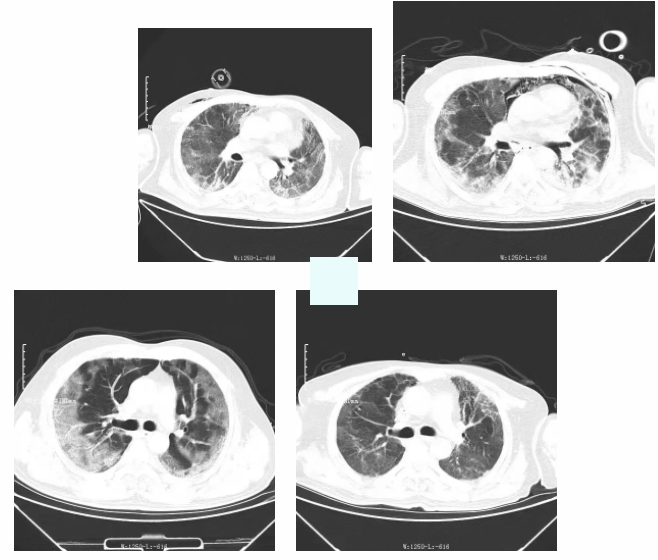

今年年初,家住鲁甸县年满51岁的x先生,因“咳嗽、咳痰、胸闷、喘息1周余,且发热2天”到我院发热门诊就诊,通过相关检查,X先生被确诊为新冠病毒感染。在经过几天的系统治疗后,X先生的病情仍未见好转,随后便出现呼吸衰竭症状,ARDS,肺部CT显影双肺近乎全白。当时情况十分危急,于是当值医师即刻反应,让X先生从普通病房转入重症医学科进行紧急救治。

“在这段时间内患者多次病危,并发了纵隔气肿,气胸,肺部难治性混合感染,血氧饱和度最低的时候低至40%,我们针对他的情况精确调整了呼吸机参数实施肺保护性通气策略,20余天长程采用俯卧位通气、抗感染治疗,行气管切开、纤支镜下肺泡灌洗,进行肺复张,每日床旁超声评估,对其进行免疫调节,营养支持,重症康复等多种治疗手段,使得患者的病情逐渐趋于稳定。”